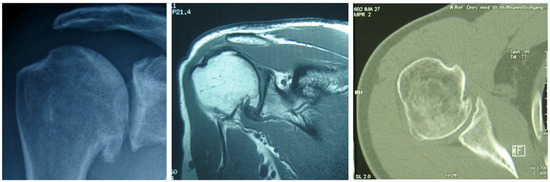

2. Physical Examinations

3. Diagnostic Radiology